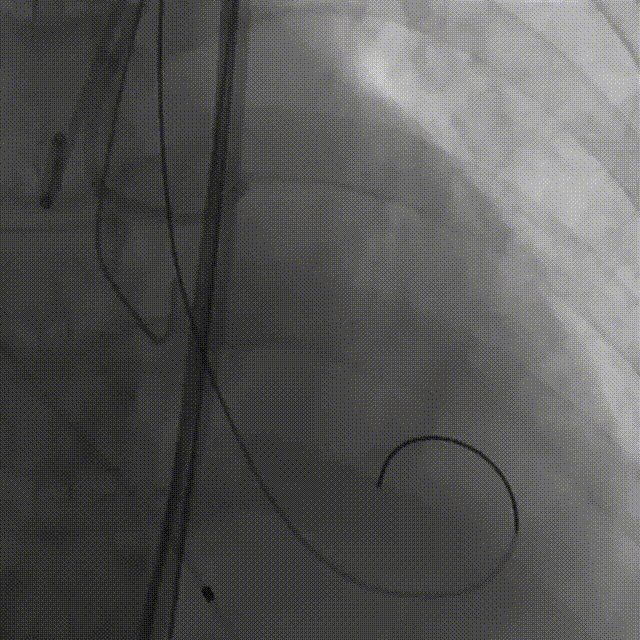

1.主动脉根部造影

2.18mm球囊预扩

3.左冠造影

4.左冠行支架保护